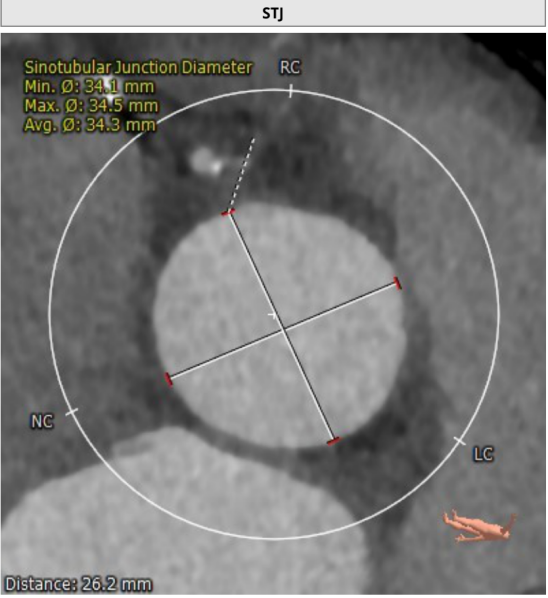

患者主动脉根部、冠状动脉、主动脉增强CT扫描,通过专业评估软件分析提示该患者主动脉瓣为功能型二叶瓣、中度钙化,左右冠窦可见融合、瓦氏窦结构较大,左右冠开口高度尚可,升主动脉最宽处约42.9mm,左室明显扩大。主动脉瓣环平均径约26.3mm,流出道平均径约27.5mm,STJ平均径约34.3mm,双侧股动脉直径均大于6mm。冠脉见钙化灶,钙化积分总和为1590.2;冠脉CTA提示:“左主干、三支冠状动脉粥样硬化改变,局部管腔可见40~60%狭窄”。

窦管交界处;34.3mm